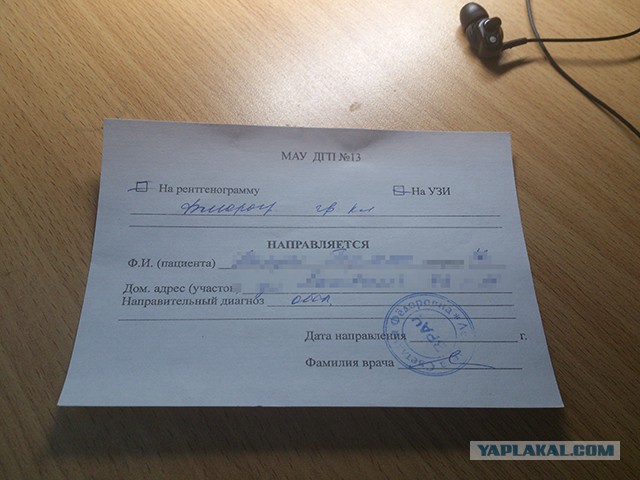

Фотографии рентгеновских снимков без необходимости направления от врача